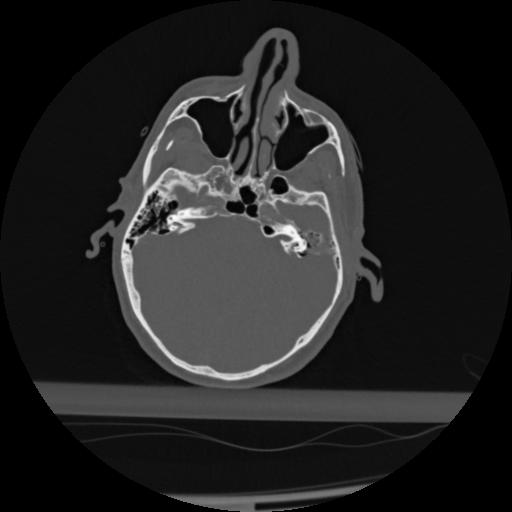

22 ANGIO,CE,Vol,0.5,ANGIO,,